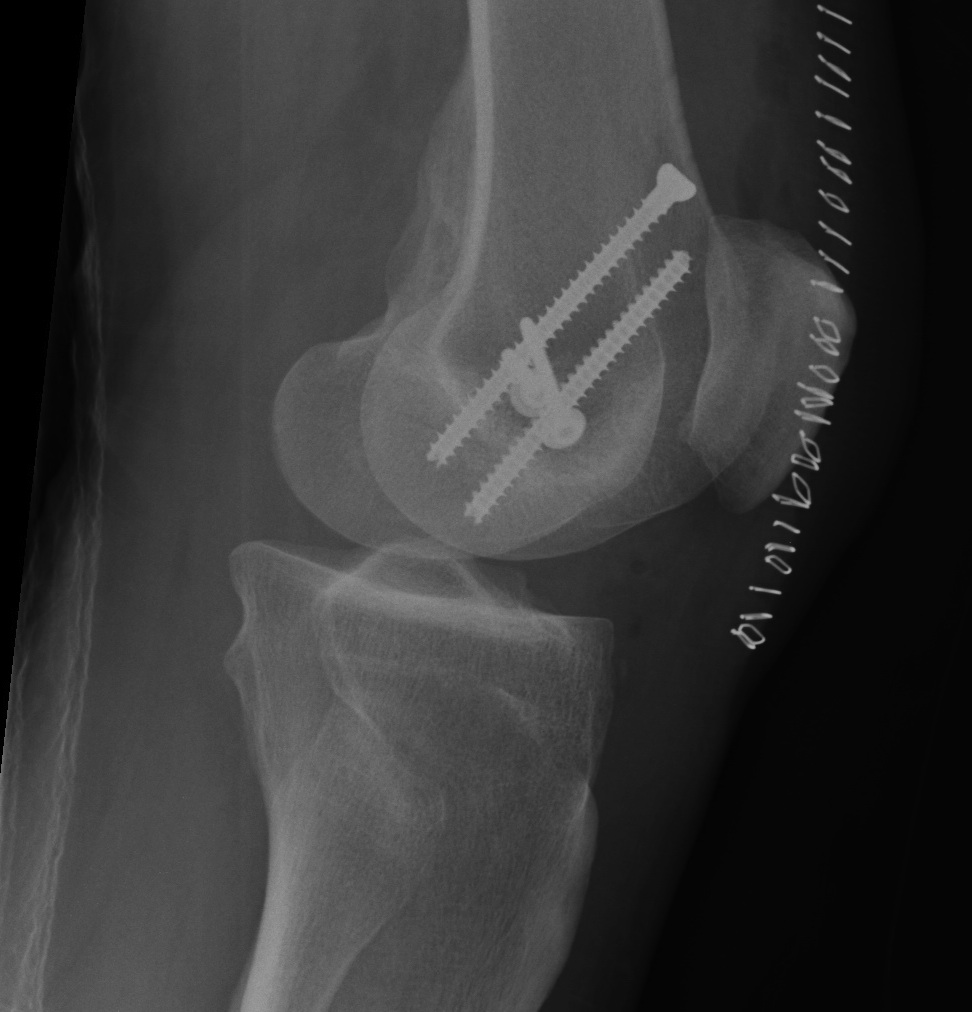

1.  AP screws

Hoffa Fracture ORIF APHoffa Fracture Lateral

3.  Combined

Hoffa fracture